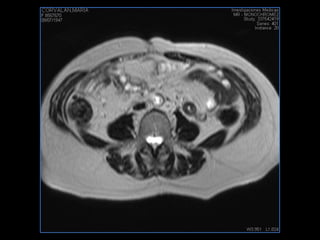

PROTOCOLO abdomen COR T2, AXIAL supresion grasa AX T1 +SAG T2  CON   GADOLINIO :  COR T1+AX T1(DIN) SAT: NO  FASE: RL THK: 6MM  COIL:  GAP: (FACTOR 1.4) 2MM FOV: 40 CM NEX:2 SINCRONIZACION RESPIRATORIA EN 3 O 4 CICLOS ALE

resonancia de abdomen